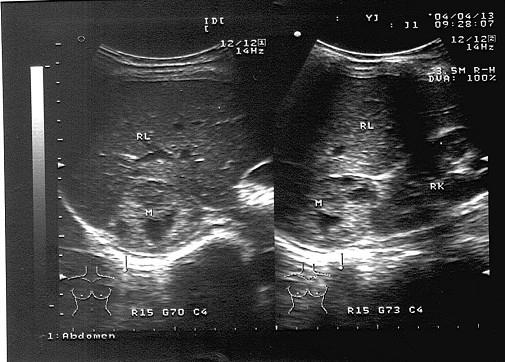

问题 女性,41岁,有阵发性高血压病史,超声检查如图所示,该病例最可能诊断?(?)

选项 A.腺瘤 B.肾脏肿瘤 C.嗜络细胞瘤 D.髓样脂肪瘤 E.肾上腺转移瘤

答案 C